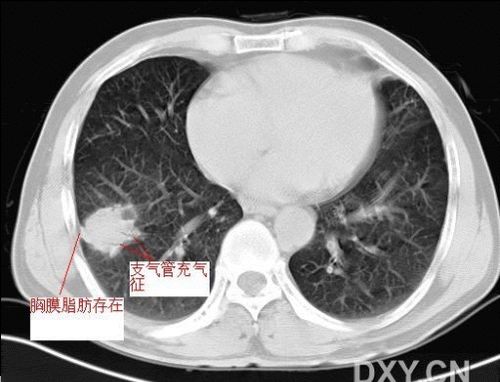

球形肺炎是大叶性肺炎的一种特殊表现[1],以肺的渗出实变为主。它的机理未明,可能是由于抗生素的广泛应用,大叶性或节段性肺炎发展受到限制而形成球形,其形成又与病缘菌的毒性数量及机体的免疫能力有关。病人多有感然症状,某些病人无明显感然症状。病变呈球形或椭圆形,大小不等,病灶密度多均匀,ct值稍低于软组织密度;或中央密度高,边缘密度低,显示晕圈状改变;有时可见空洞[2]。病灶边缘比较规则,也可不规则,有毛刺或呈锯齿状改变,但较模糊。位于肺周区,贴近胸膜,部分病栽表现为两侧缘垂直于胸膜,呈刀切样平直边缘。病灶周围血管纹理增多、增粗、常有局限性胸膜增厚。球形肺炎抗炎两周后,病灶即有缩小,最后能完全吸收。

球形肺炎:病变密度相对较淡,中央密度略高,ct图片上密度较为均匀,增强中央可出现无强化区。病变邻近胸膜反应较为显著,可表现为增厚、粘连(可以比较广泛),病变内可以见到大血管的贯穿,周围及近肺门侧可以见到血管纹理增多、增粗,可有支气管充气征象,两侧可垂直于胸膜或呈方形,边缘可为刀切征,它可以出现毛刺样的类似改变,短期内抗炎治疗有效。